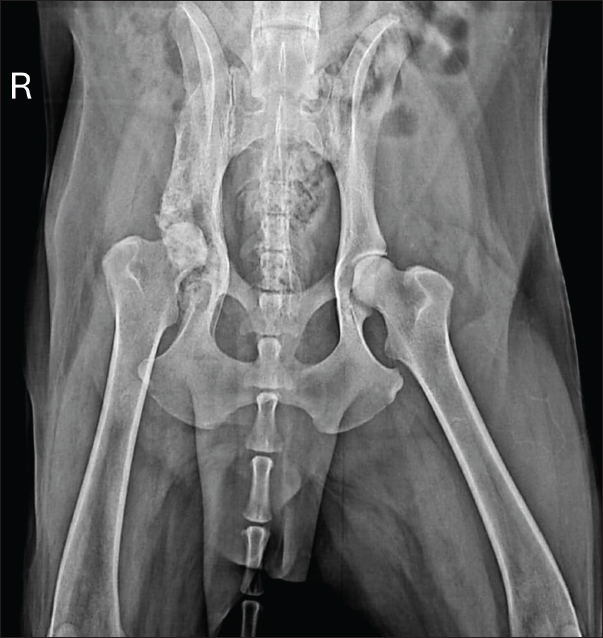

Radiographic examination revealed marked periosteal bone proliferation with extensive areas of osteolysis affecting the wing and body of the ilium, acetabulum, and right femur’s head and neck, along with adjacent soft tissue swelling (Fig. 1).

Fig. 1. Radiographic examination of the dog showing periosteal bone proliferation and areas of osteolysis (arrows) in the right wing and body of the ilium and acetabulum, accompanied by adjacent soft tissue swelling.